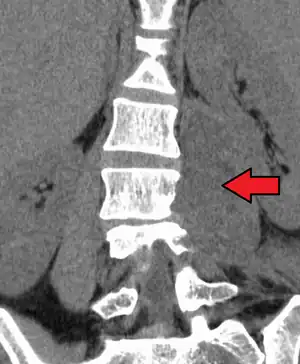

Psoas muscle abscess

Psoas abscess is a collection of pus in the iliopsoas muscle compartment.[1][2] It can be classified into primary psoas abscess (caused by hematogenous or lymphatic spread of a pathogen) and secondary psoas abscess (resulting from contiguous spread from an adjacent infectious focus).[2]

| Paraspinal abscess in the psoas muscle | |

Psoas abscess may be caused by lumbar tuberculosis. Owing to the proximal attachments of the iliopsoas, such an abscess may drain inferiorly into the upper medial thigh and present as a swelling in the region. The sheath of the muscle arises from the lumbar vertebrae and the intervertebral discs between the vertebrae. The disc is more susceptible to infection, from tuberculosis and Salmonella discitis. The infection can spread into the psoas muscle sheath.[3]